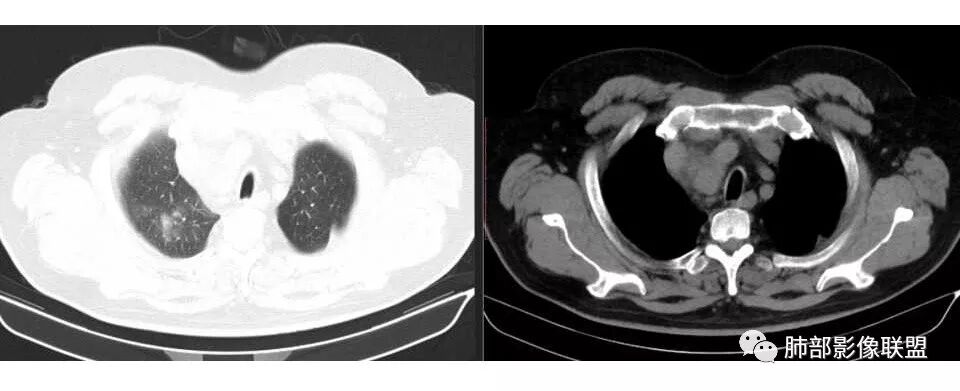

南边: 肺内,靠近纵隔,然后病灶与纵隔分界不清,也就是说与纵隔肿大淋巴结融合一起,或侵犯纵隔了

或者说紧贴纵隔胸膜,定位不易

他的病理:多为小细胞癌,其次腺癌、鳞癌

这么大,肺门区,如果纵隔型肺癌,按理是中央型,常规——支气管为主

这一例表现反了,支气管稍受侵犯

宇宙星空: 嗯,淋巴结肿大为主

南边: 而且肺癌,一定受叶段的局限,这一例跨越右肺门,提示多个淋巴结融合

南边: 例如这个病灶,如果是一个孤立的肿块,边界清晰,提示破坏性不强,不应该是包绕支气管,是推移到一边为主,这个表现为包绕,提示是多个病灶融合